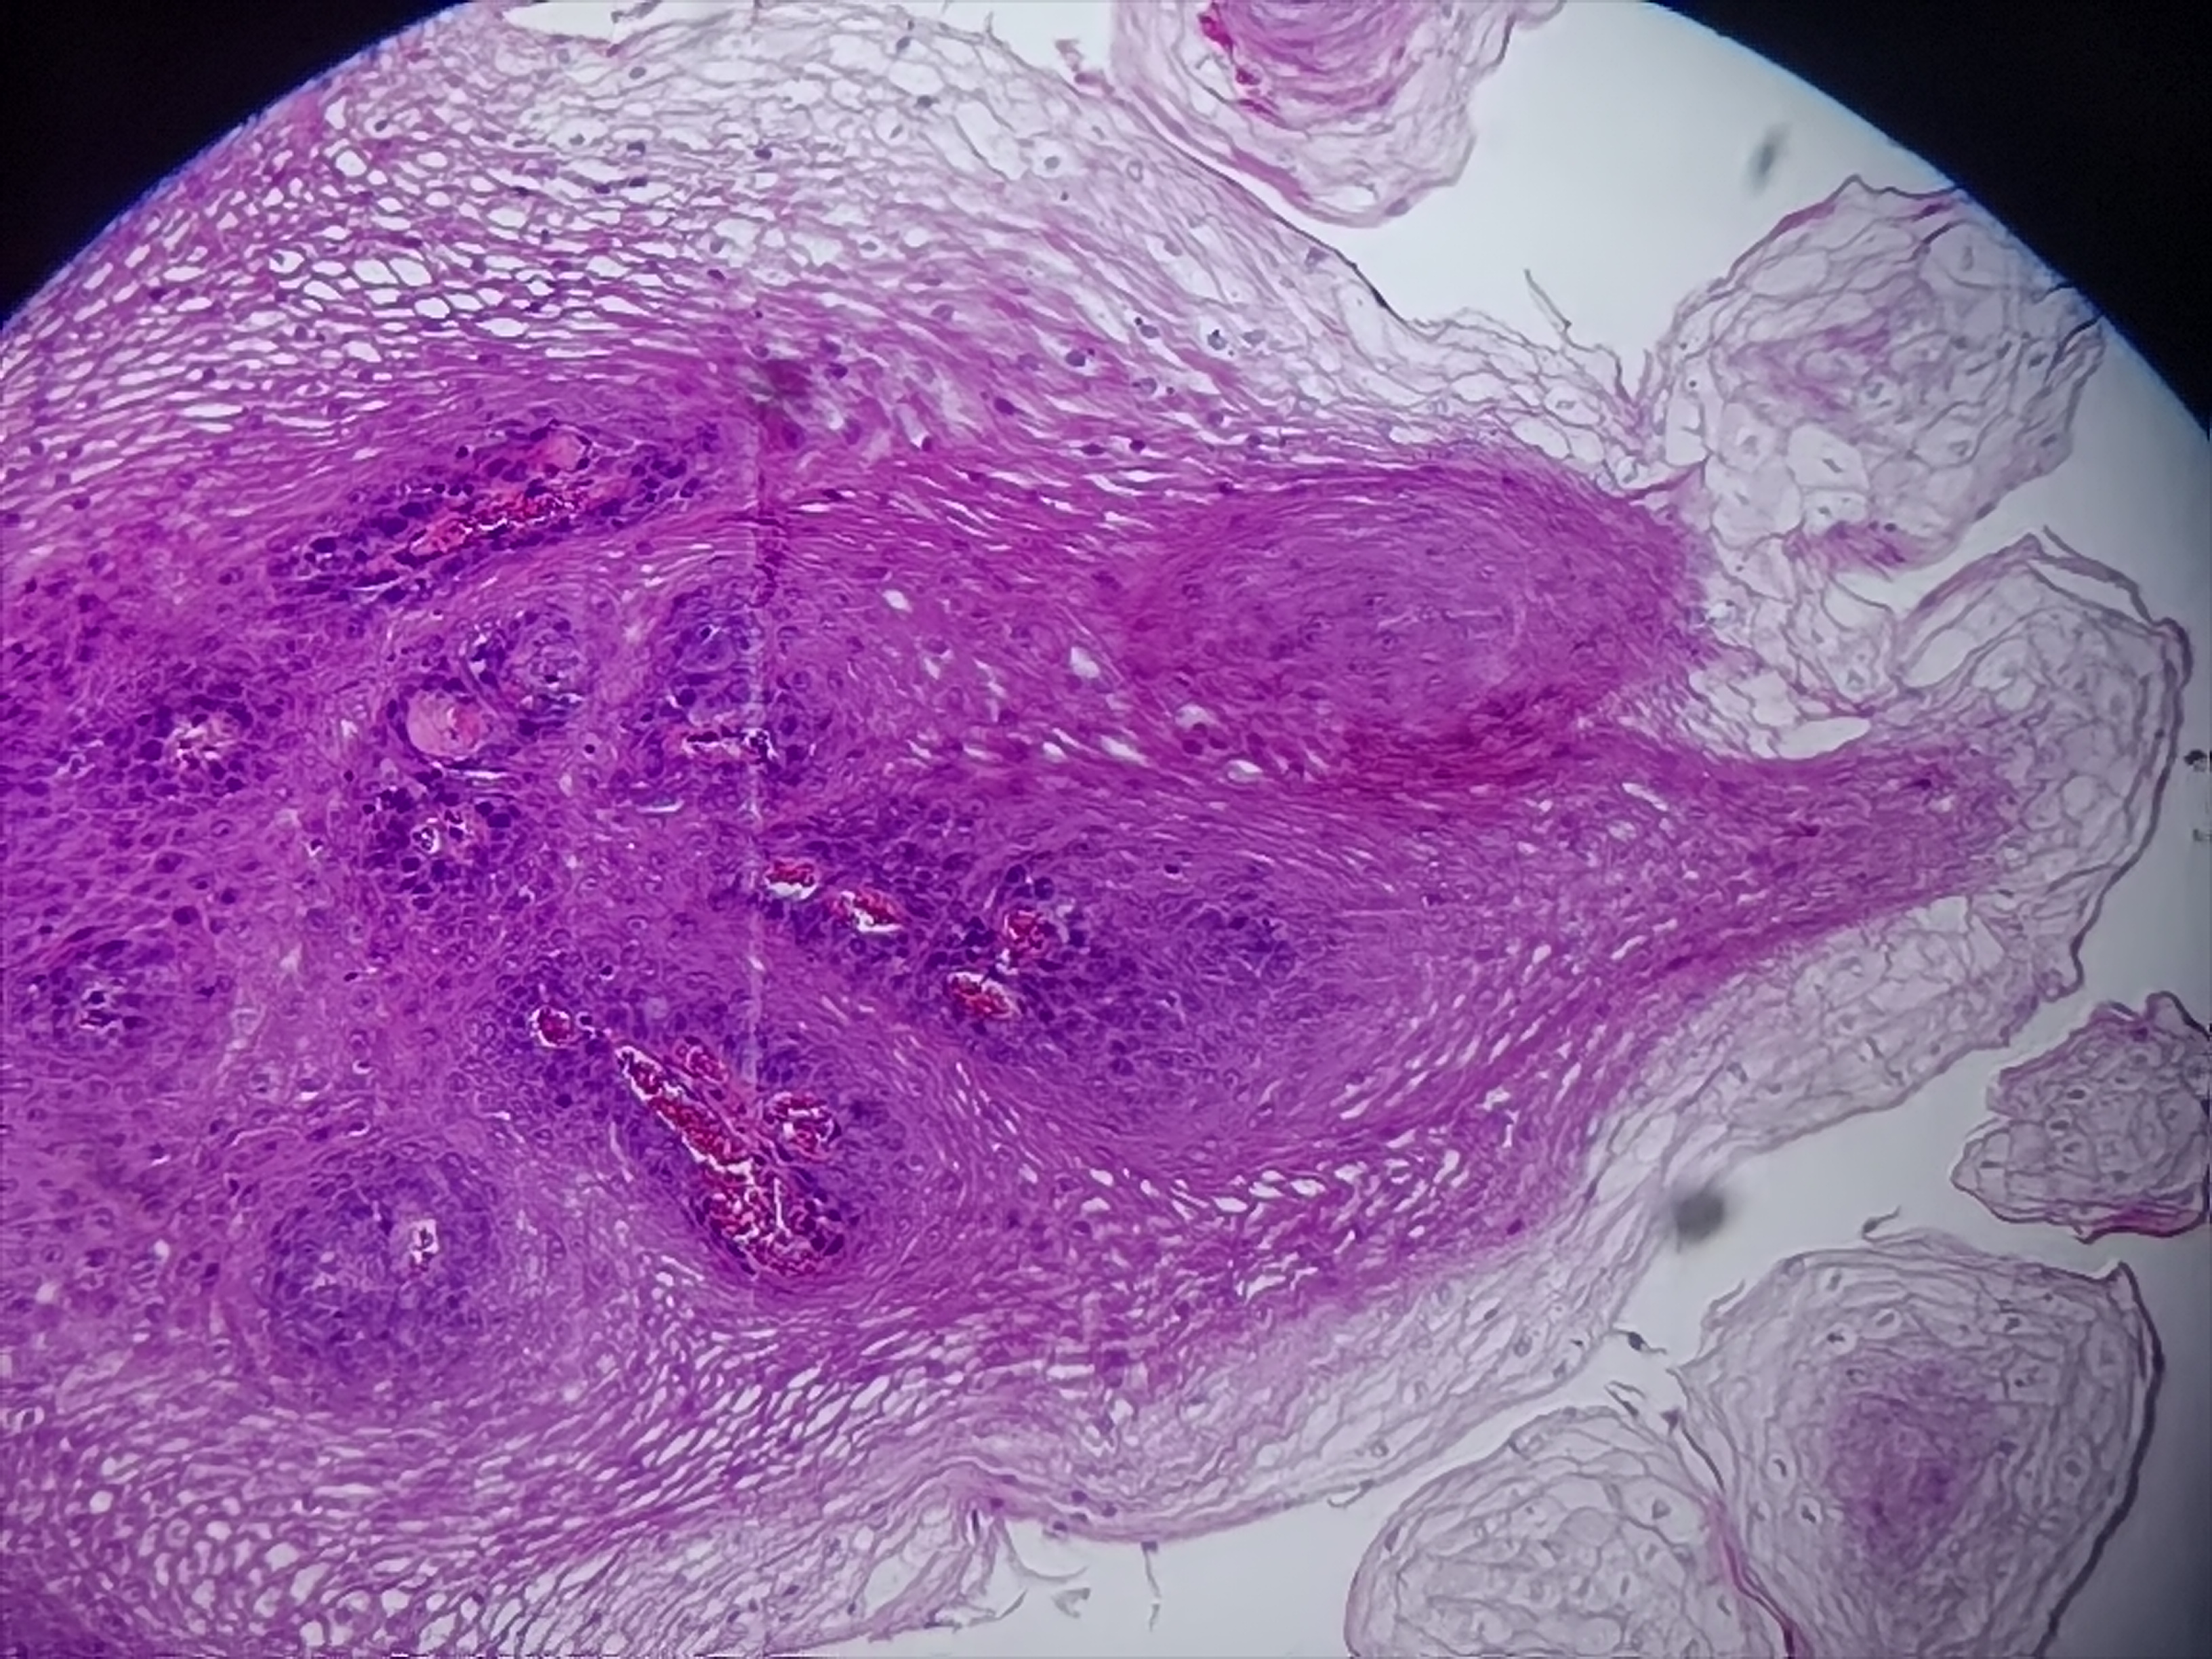

食管活检

性别

男

年龄

55岁

临床诊断

食管乳头状瘤

一般病史

食管距门齿30cm处可见一隆起

标本名称

食管粘膜活检

大体所见

灰白色组织1块

符合鳞状细胞乳头状瘤

鳞状上皮乳头状瘤。